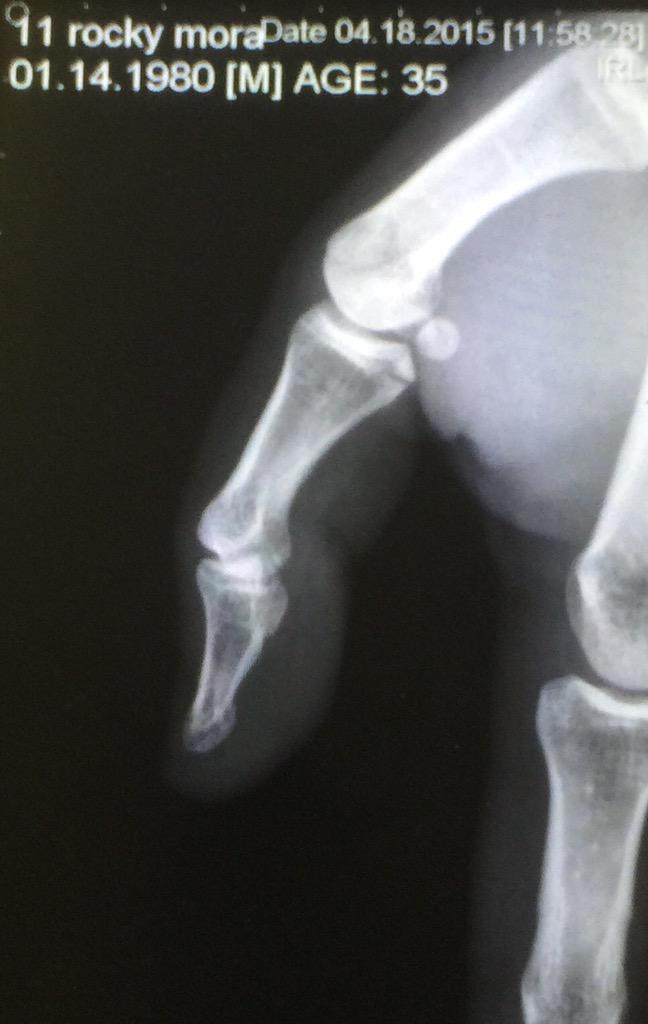

Luego de accidentarse durante la segunda sesión de prácticas en el circuito urbano de Long Beach, el estadounidense de 35 años se rompió un dedo pulgar, por lo que no podrá debutar en la categoría.